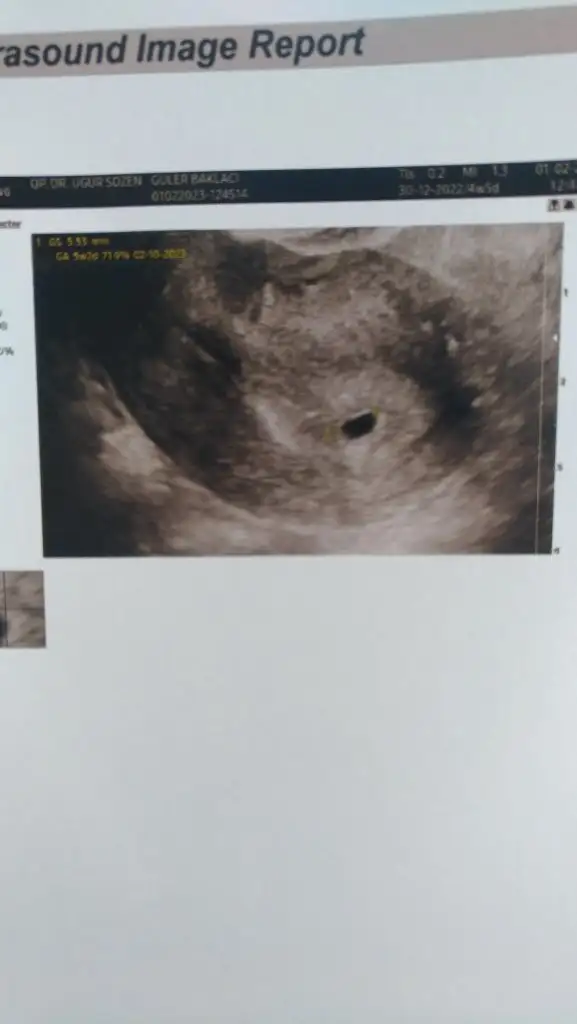

Arkadaşlar merhaba ben 26 ocakta 2 adet 5. Gün embriyosu transferi oldım bugün 6. Günüm dayanamadım test yaptım çok ince çizgi çıktı acaba kuruma çizgisi mi erken mi test için 🥹🥹🙏